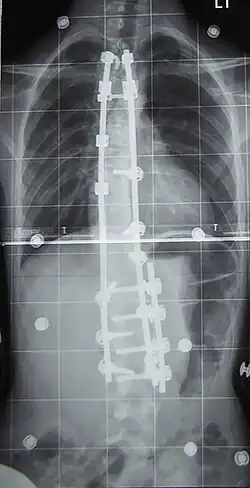

Surgery is usually recommended by orthopedists for curves with a high likelihood of progression (i.e., greater than 45–50° of magnitude), curves that would be cosmetically unacceptable as an adult, curves in people with spina bifida and cerebral palsy that interfere with sitting and care, and curves that affect physiological functions such as breathing.[104][105]

Surgery is indicated by the Society on Scoliosis Orthopaedic and Rehabilitation Treatment (SOSORT) at 45–50°[4] and by the Scoliosis Research Society (SRS) at a Cobb angle of 45°.[106] SOSORT uses the 45–50° threshold as a result of the well-documented, plus or minus 5° measurement error that can occur while measuring Cobb angles.[106]

Surgeons who specialize in spine surgery perform surgery for scoliosis. To completely straighten a scoliotic spine is usually impossible, but for the most part, significant corrections are achieved.[107]

The two main types of surgery are:[108]

- Anterior fusion: This surgical approach is through an incision at the side of the chest wall.

- Posterior fusion: This surgical approach is through an incision on the back and uses metal instrumentation to correct the curve.

One or both of these surgical procedures may be needed. The surgery may be done in one or two stages and, on average, takes four to eight hours.

In 1962, the American orthopaedic surgeon Paul Harrington introduced a metal spinal system of instrumentation that assisted with straightening the spine, as well as holding it rigid while fusion took place. The now obsolete Harrington rod operated on a ratchet system, attached by hooks to the spine at the top and bottom of the curvature that, when cranked, would distract—or straighten—the curve. The Harrington rod obviates the need for prolonged casting, allowing patients greater mobility in the postoperative period and significantly reducing the quality of life burden of fusion surgery. The Harrington rod was the precursor to most modern spinal instrumentation systems. A major shortcoming was that it failed to produce a posture wherein the skull would be in proper alignment with the pelvis, and it did not address rotational deformity. As the person aged, there would be increased wear and tear, early onset arthritis, disc degeneration, muscular stiffness, and acute pain. "Flatback" became the medical name for a related complication, especially for those who had lumbar scoliosis.[119]

In the 1960s, the gold standard for idiopathic scoliosis was a posterior approach using a single Harrington rod. Post-operative recovery involved bed rest, casts, and braces. Poor results became apparent over time.[120]

In the 1970s, an improved technique was developed using two rods and wires attached at each level of the spine. This segmented instrumentation system allowed patients to become mobile soon after surgery.[120]

In the 1980s, Cotrel–Dubousset instrumentation improved fixation and addressed sagittal imbalance and rotational defects unresolved by the Harrington rod system. This technique uses multiple hooks with rods to give stronger fixation in three dimensions, usually eliminating the need for postoperative bracing.[120]